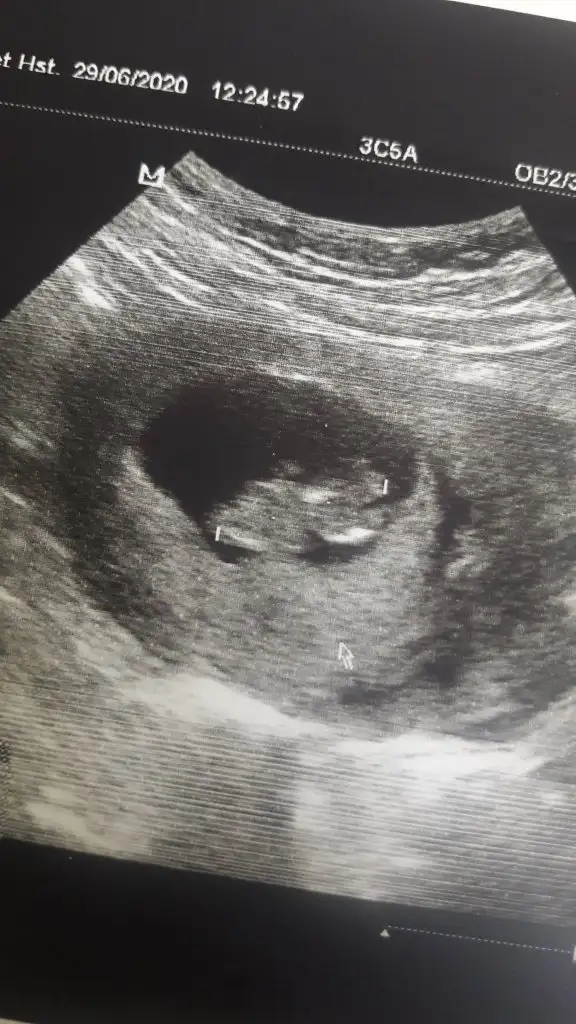

dr soylemeden siz gorun genital nub teorisi ( bebegin cinsiyeti)

Merhabalar bende yarın doktora gideceğim bakalım varmi bir yorumunuz bana da :)

Eklentiler

• image.webp